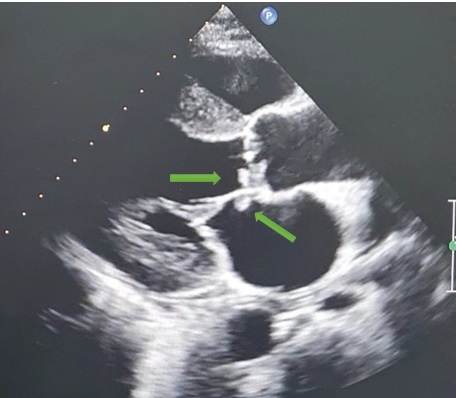

Siêu âm tim bệnh nhân D. thấy các nốt sùi như nụ hoa trên cành cây (mũi tên xanh) tại van động mạch chủ và van hai lá.